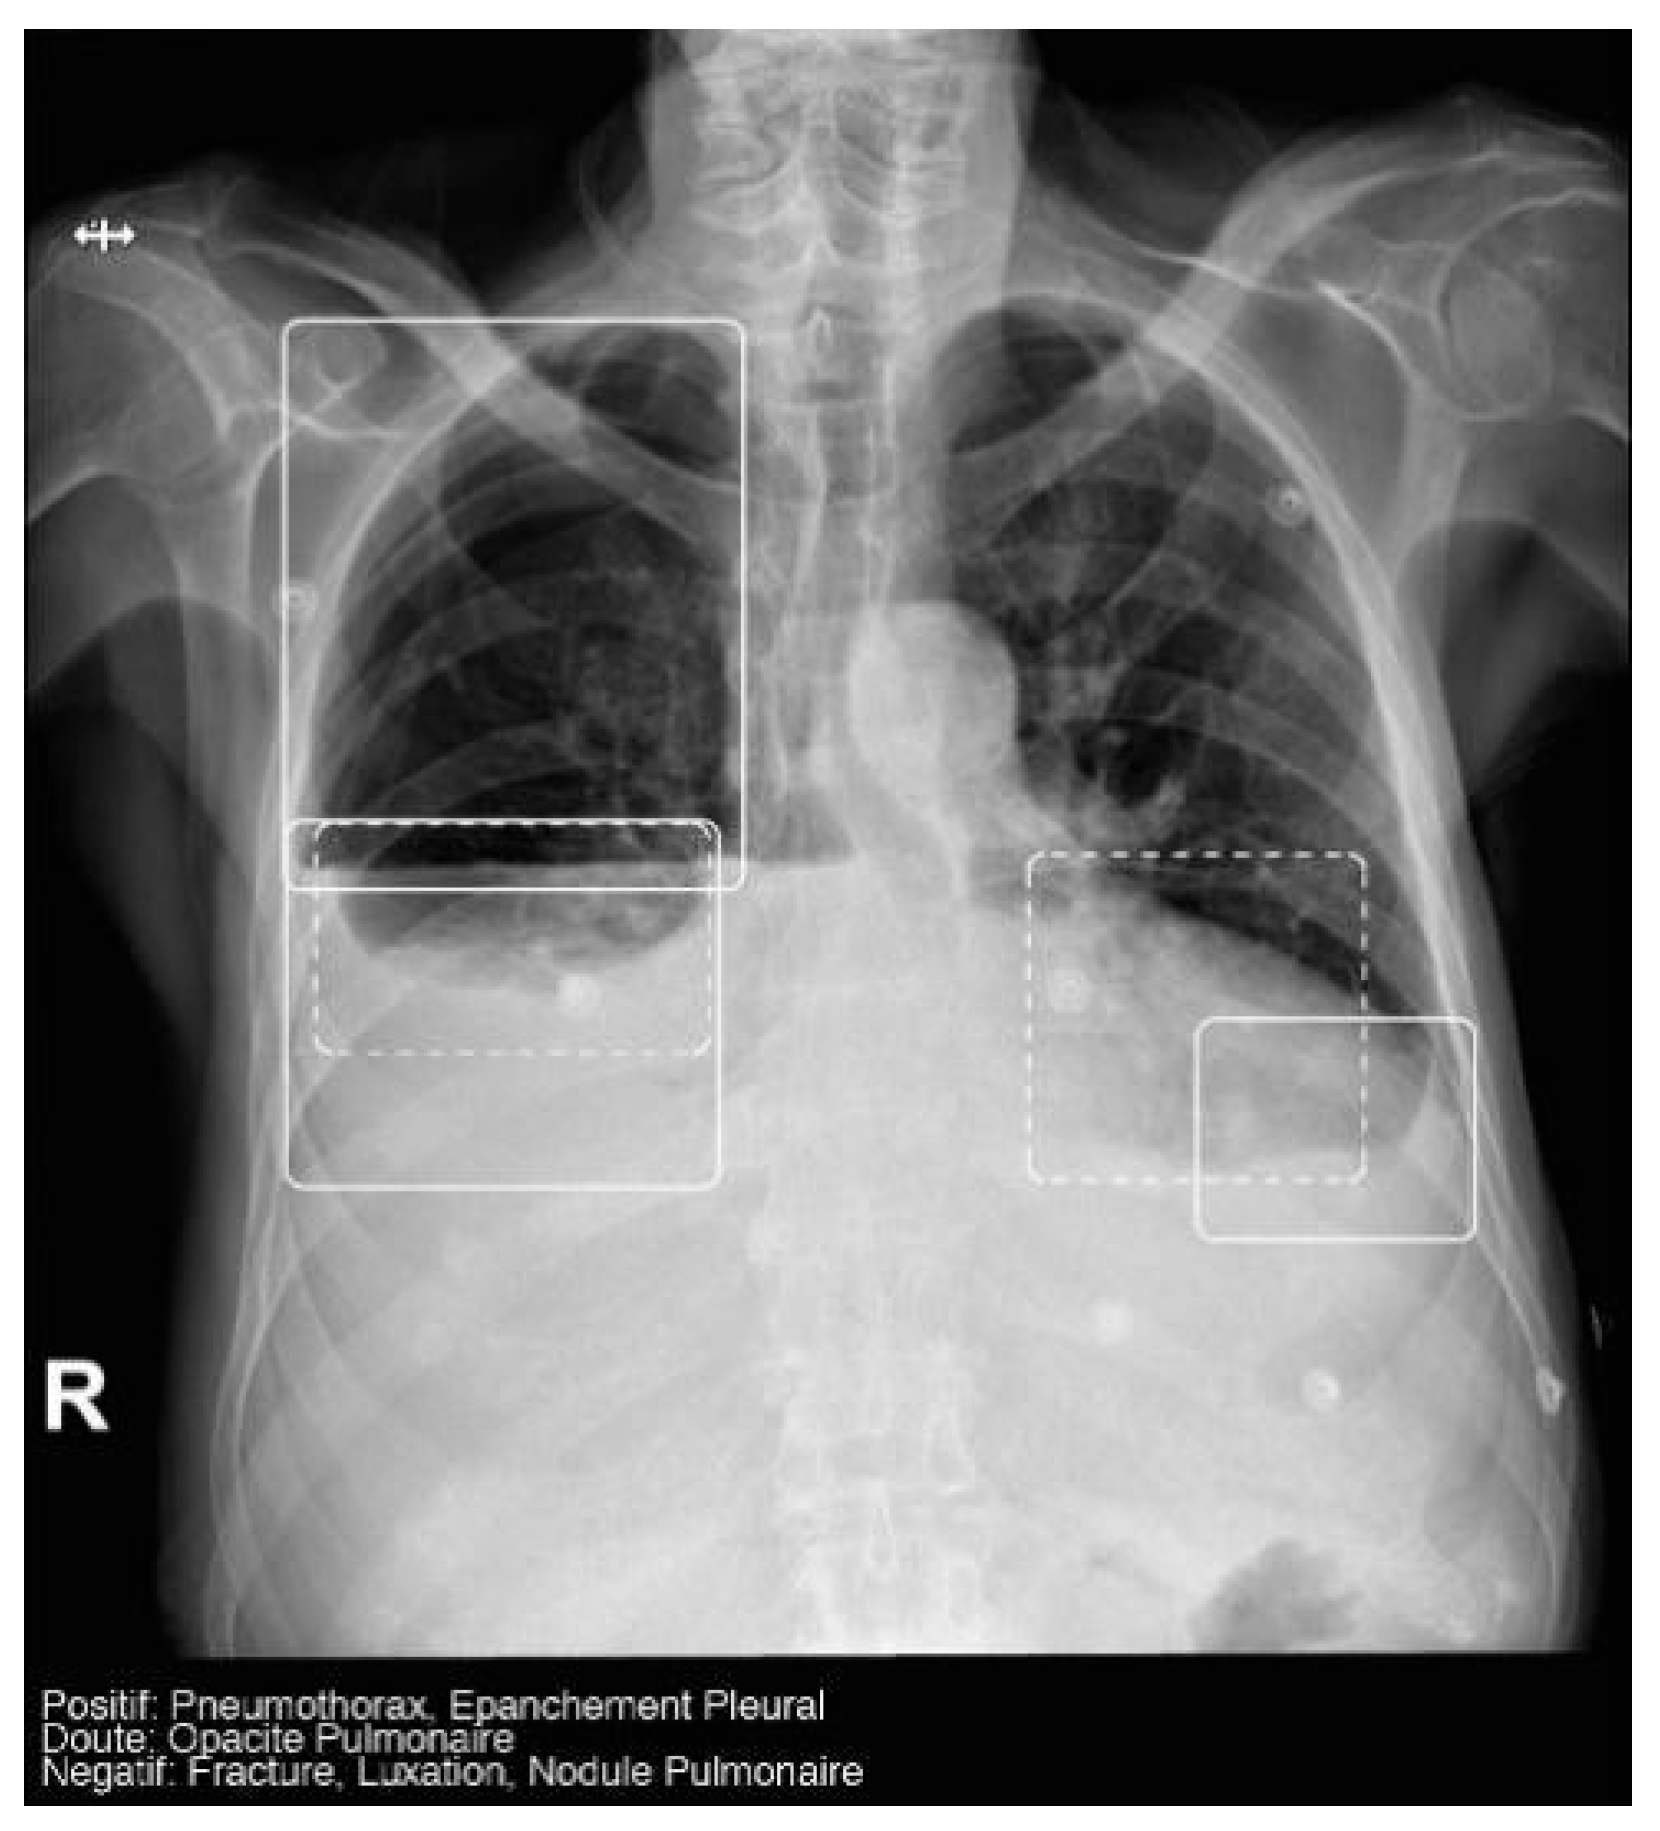

The AI software (Arterys Chest MICA v29.4.0, developed by Arterys, a company based in Paris, France) was the World’s First Online Medical Imaging Platform 100% Cloud native, powered by AI and FDA cleared. It was a clinical application (CE marked as a Class IIa medical device) designed to process thoracic radiographic series and identify five imaging findings (categorical variables): pulmonary nodule, pulmonary opacity, pleural effusion, pneumothorax, and fracture. Each detected finding was localized in the image using a bounding box and was assigned a confidence label, either “positive” (continuous line) or “doubtful” (dashed line). Moreover, the algorithm provided a list of findings not detected in the current radiographic view (Figure 2). All findings were detected by a deep learning model that processed all radiographic views included in the series.

Figure 2.

Chest radiograph with AI analysis, which detected a positive right pneumothorax, positive bilateral pleural effusion (both outlined with continuous boxes), and doubtful bibasilar opacities (outlined with discontinuous boxes).